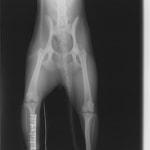

ペルシャ猫 11ヶ月齢 雄

他院にて左大腿骨遠位の成長板骨折(salter-harrisⅠ型)が認められており、治療相談を目的として来院。当院にて、キルシュナーワイヤーを用いたピンニングにより骨折部位の整復を行いました。術後の経過は良好で、現在も経過観察中です。

術前レントゲン